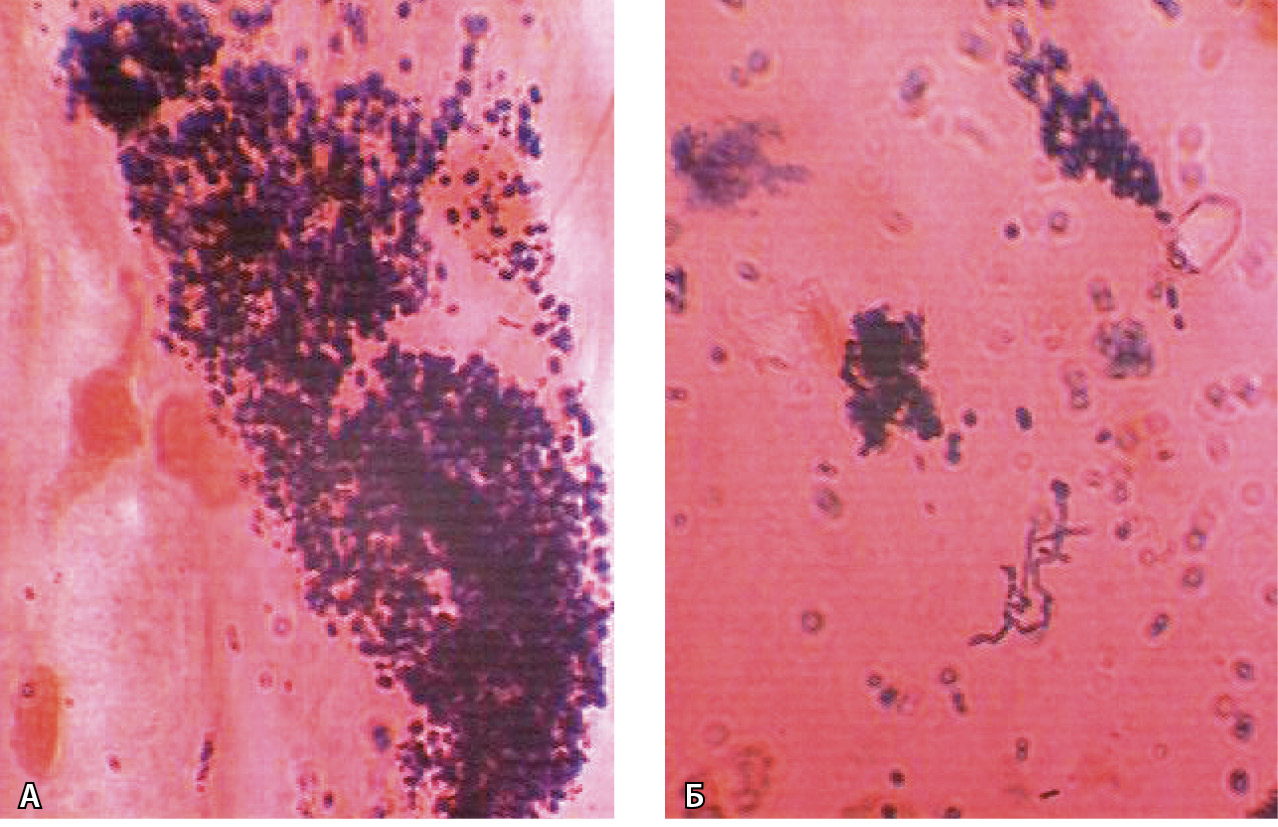

Длительное применение ИПП вызывает такие гистопатологические изменения слизистой оболочки желудка, как гиперплазия париетальных клеток с выпячиванием их в просвет железы, кистозная дилатация фундальных желез и гиперплазия фовеолярного эпителия (рис. 3). При эндоскопическом исследовании эти изменения выявляются в виде полипов фундальных желез (рис. 4), гиперпластических полипов, множественных приподнятых поражений, булыжноподобной слизистой оболочки [11]. Клиницисты не всегда уделяют должное внимание этой проблеме. Вместе с тем установить клиническую значимость данных поражений можно только на основании результатов долгосрочных проспективных исследований [12].

Рис. 3. Гастропатия, индуцированная приемом ингибиторов протонной помпы: дистрофия и вакуолизация париетальных клеток в главных железах желудка (А), гиперплазия нейроэндокринных клеток и участки пилорической метаплазии в главных железах желудка (Б). Окраска гематоксилином и эозином; × 500 (из личного архива С.Г. Хомерики)